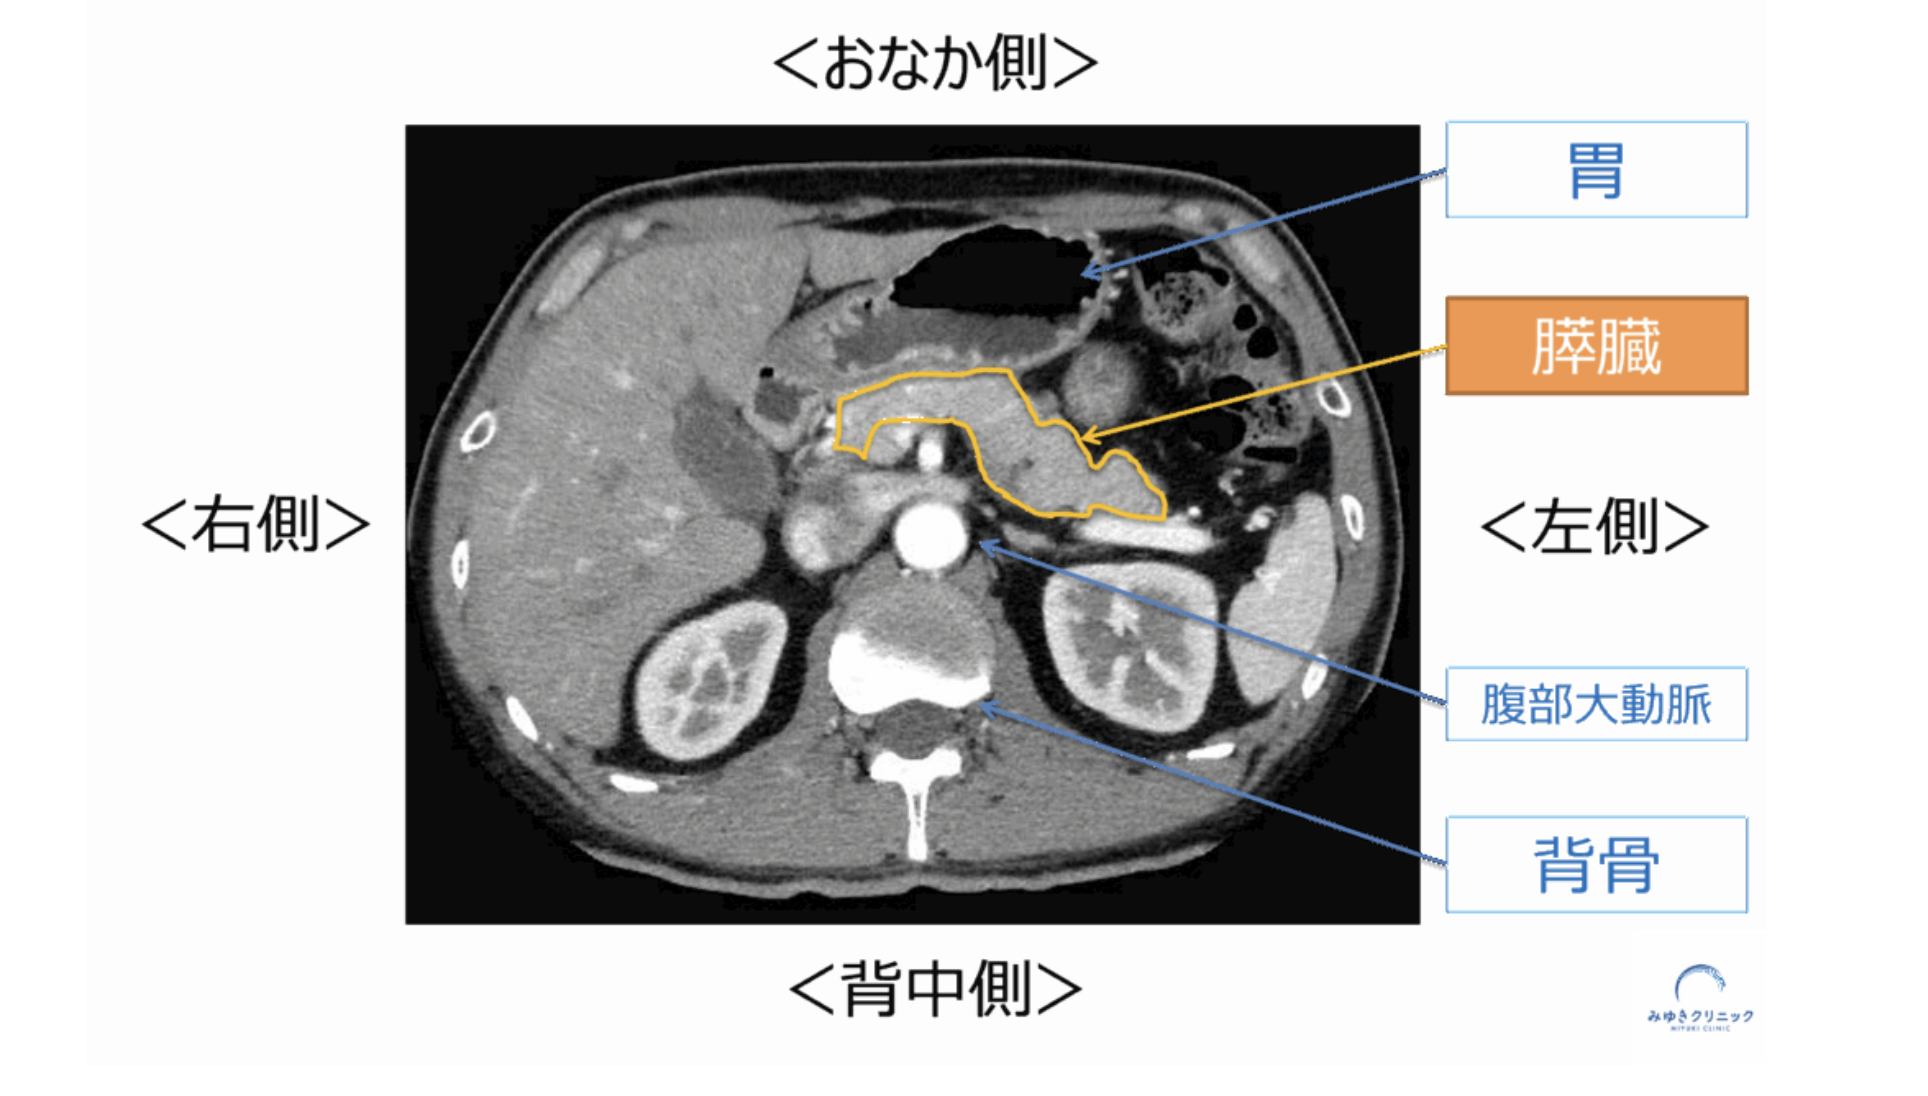

膵臓は胃の裏側、体の奥に位置する臓器です。 そのため、小さな腫瘍ができても周囲の臓器や神経に影響しにくく、症状として現れにくいと考えられています。

膵がんが初期に症状を出しにくい理由を示した図

膵臓は体の奥に位置するため、小さな異常では症状が出にくいことがあります。

膵臓は胃の裏側、背骨の前に位置しています。 そのため、膵がんでは背中(特に左側)に痛みを感じることがあります。